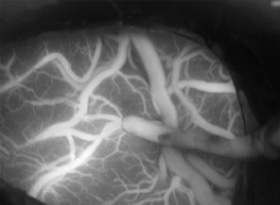

術中ICG蛍光造形1

術中ICG蛍光造形1

術中ICG蛍光造形2

術中ICG蛍光造形2

術中ICG蛍光造形3

術中ICG蛍光造形3